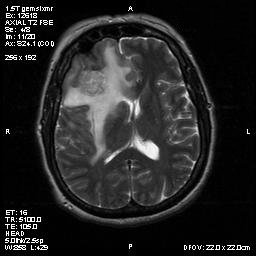

T1-weighed MR images demonstrate an extraaxial, dural based mass involving the right supraorbital region  (Panel A and B). The mass shows homogeneous enhancement  (Panel C). CT scan demonstrates as well as rim calcification (Panel E). On T2-weighed imagers, significant vasogenic edema is demonstrated despite the small size of the lesion and the extraaxial location (Panel D).